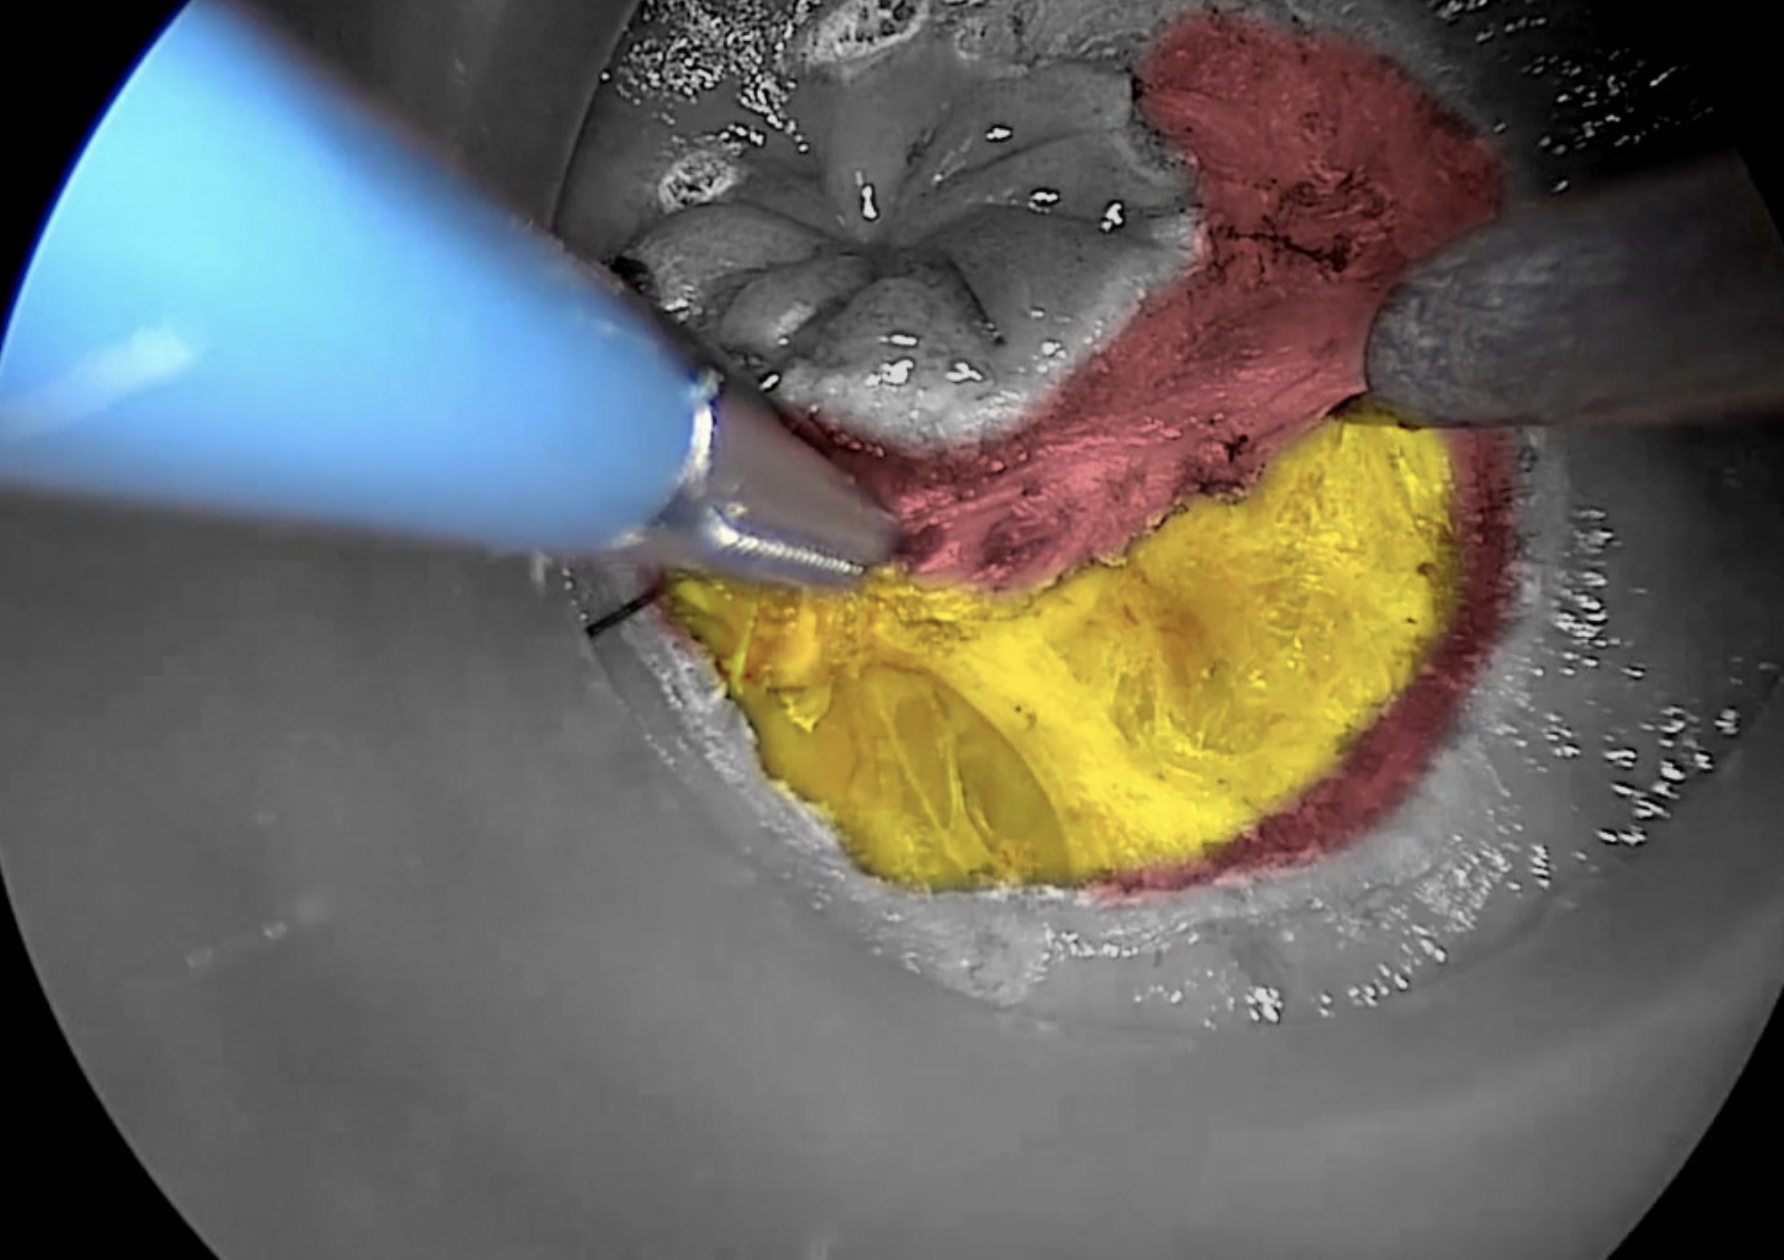

Before commencing dissection, it is our preference to mark the rectal mucosa circumferentially, using a conventional diathermy hook, just distal to the secured purse-string stitch. A full thickness incision of the rectal wall is started at the postero-lateral aspect, at either the 5 or 7 o’clock position.

Copyright Dr. Joep Knol

Diathermy marking of rectal mucosa to guide initial dissection. The contrast picture shows the distal rectal excision margin.